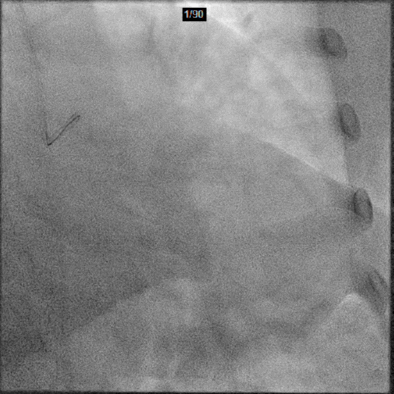

Angiography-LCA

AP/CAU 3.3mL

AP/Cr 3.4mL

CAG造影剂用量:10.1mL